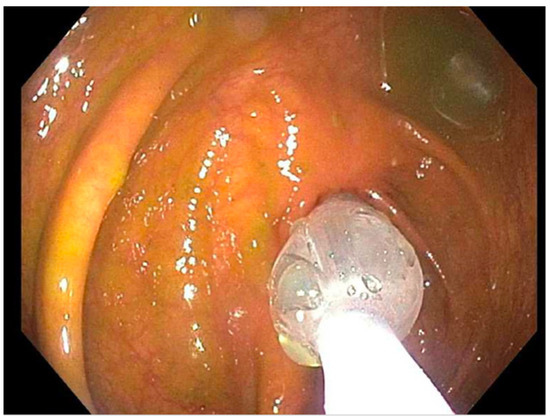

| 1 | (2019: Remicade 10 mg) (2019: Humira 40 mg) (2020: Humira 80 mg subcutaneous) | November 2019, dilated (b) TI from (12 to 18 mm) (a) TI stricture dilated to (16.5 mm) | November 2020, dilated TI to (20 mm) | March 2023, laparoscopic assisted ileocecectomy |

| 2 | (2019: prednisone 40 mg) (2019: Remicade 5 mg) (Remicade 10 mg) | September 2019, ICV dilated from (8 to 11 mm) | December 2020 and August 2021 ICV dilated from (9 to 18 mm) then (12 to 18 mm) | June 2022, ICV dilated from (13.5 to 20 mm) |

| 3 | (2019: prednisone 20 mg BID w/mesalamine 500 mg TID) (2020: 6-MP 50 mg) (2021: Humira 40 mg/MTX 25 mg) | February 2021, PAC dilated from (7 to 15 mm) | August 2021, PAC dilated from (15 to 20 mm) | August 2022, mucosal narrowing stretched to 20 mm without noted renting |

| 4 | (2021: Humira 40 mg every other week/steroid 40 mg daily, escalated to Humira 40 mg weekly) (2022: MTX 25 mg) | September 2022, dilation of the ICV from (4 to 13.5 mm) (food bezoar noted) | November 2022, ICV dilated from (8 to 15 mm) | December 2022, ICV dilated (12 to 15 mm) |